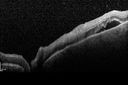

Toxoplasmosis Retinitis - Vitritis and Anerior Uveitis420 viewsSerous Retinal Detachment Associated with Lesion00000

Toxoplasmosis Retinitis - Vitritis and Anerior Uveitis456 viewsSerous Retinal Detachment Associated with Lesion00000

Toxoplasmosis Retinitis - Vitritis and Anerior Uveitis436 viewsSerous Retinal Detachment Associated with Lesion00000